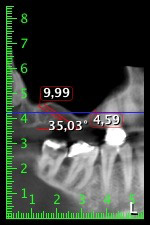

Die 59-jährige Patientin wurde mit einer fortgeschrittenen Parodontitis vorstellig, beschrieb ein ungutes Gefühl und einen schlechten Geschmack ausgehend vom ersten Quadranten distal. Die klinische Untersuchung zeigte allgemein erhöhte Taschentiefen und einen stark fortgeschrittenen Knochenabbau in regio 16 und 14. Die radiologische Untersuchung untermauerte den Befund (Abb. 1). Die Zähne 16 und 14 waren nicht zu erhalten.

Abb.1: Orthopantomogramm mit Knochenabbau in Regio 16–14.*

Etwa sechs Monate nach Extraktion der Zähne 16 und 14 wurde zur Planung und Risikominimierung eine digitale Volumentomografie (DVT, Planmeca) erstellt. Hierbei wurde deutlich, dass der Knochen sich nicht in der gewünschten Quantität regeneriert hat (Abb. 2 bis 7).

Abb. 2 bis 7: DVT mit stark reduziertem horizontalen Knochenangebot.